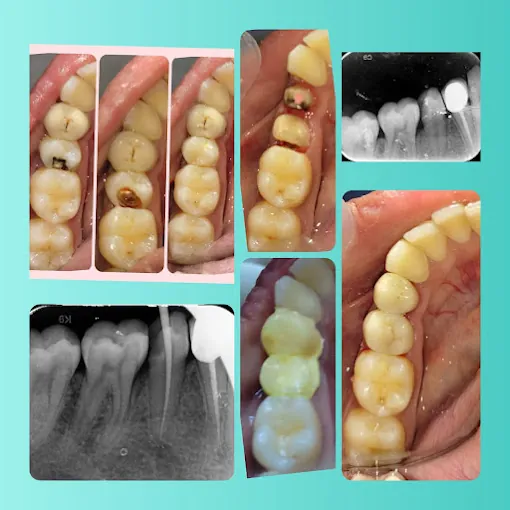

Bunny Teeth Advanced Dentistry in T Nagar offers top-quality general dentistry, from preventive care to restorations. Our experienced team uses modern tools to ensure your oral health. Open Open daily from 10:30 am to 7:30 pm, reach us at or https://www.facebook.com/Thebunnyteeth/. Book now for a brighter smile!

We provide cleanings, fillings, crowns, and preventive care.

Yes, we use durable materials for long-term results.

We use digital X-rays for precise diagnostics.